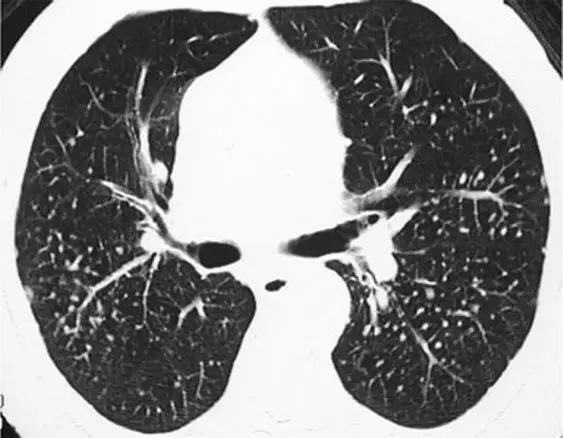

2.网状影

在HRCT上,网状图案的特征是网格的无数杂*交乱**错阴影。网状结构的成分可能是以下的全部或部分:小叶间隔增厚,小叶间质增厚,蜂窝壁囊肿,支气管周围血管间质增厚和牵引性支气管扩张/支气管扩张。典型的疾病是IPF。IPF表现为下肺野、后基底段、胸膜下为主,显著的网状蜂窝样改变。IPF和网状结构的主要鉴别疾病是NSIP,石棉肺,慢性过敏性肺炎,类风湿性关节炎,DIP和晚期结节病。

*特发性肺纤维化。下叶水平的HRCT表现为胸膜下“网状结构”,其特征是小叶间间隔增厚,小叶间质增厚,牵拉性支气管扩张和支气管扩张以及最小程度的蜂窝状。

NSIP的特征是下肺野、胸膜下为主的轻微网状状改变、毛玻璃影,几乎没有蜂窝样改变,即便有也在重叠区域。NSIP与IPF不同的是以毛玻璃改变为主,几乎没有蜂窝样改变。

*非特异性间质性肺炎。下叶水平的HRCT表现出“网状模式”,其特征是存在支气管周围血管间质增厚以及牵引性支气管扩张和支气管扩张。